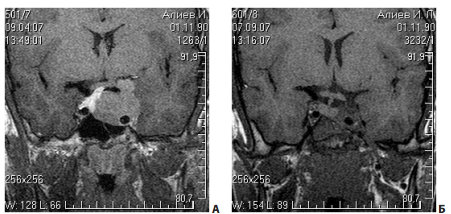

На рис. 11 представлен пример удаления гигантской эндо-супра-латероселлярной аденомы гипофиза — от задне-верхних отделов левого кавернозного синуса формировался крупный вырост опухоли с признаками старого кровоизлияния в него

Рис. 11. Пример удаления гигантской эндо-супра-латероселлярной аденомы: А, Б — КТ до операции; В, Г — МРТ до операции, Д, Е — МРТ через несколько месяцев после операции

Первым этапом была удалена эндо-супраселлярная часть опухоли под контролем 0 и 30-градусных эндоскопов. Затем под контролем 45º и 70º эндоскопов опухоль удалена из полости левого кавернозного синуса, в задних отделах синуса обнаружен вторичный узел опухоли, из его полости выделилось некоторое количество темно-бурой жидкости, после чего со стенок вторичного узла удалено небольшое количество опухоли (рис. 11, 12). При контрольной МРТ через несколько месяцев после операции явные остатки опухоли, в том числе и в полости кавернозного синуса, не определяются. Стрелкой указана складка капсулы удаленного вторичного узла.На рис. 13 представлен пример удаления большой эндо-супра-латероселлярной аденомы гипофиза. Однако, по данным контрольной КТ в первые сутки после операции, можно лишь сказать, что нами была удалена большая часть опухоли, но судить о том, есть ли остатки аденомы и какого они размера, достаточно сложно.

Рис. 12. Интраоперационный снимок этапа удаления гигантской эндо-супра-латероселлярной аденомы (45º эндоскоп): 1 — проекция левого зрительного нерва; 2 — капсула супраселлярного отдела опухоли; 3 — задне-верхние отделы левого кавернозного синуса